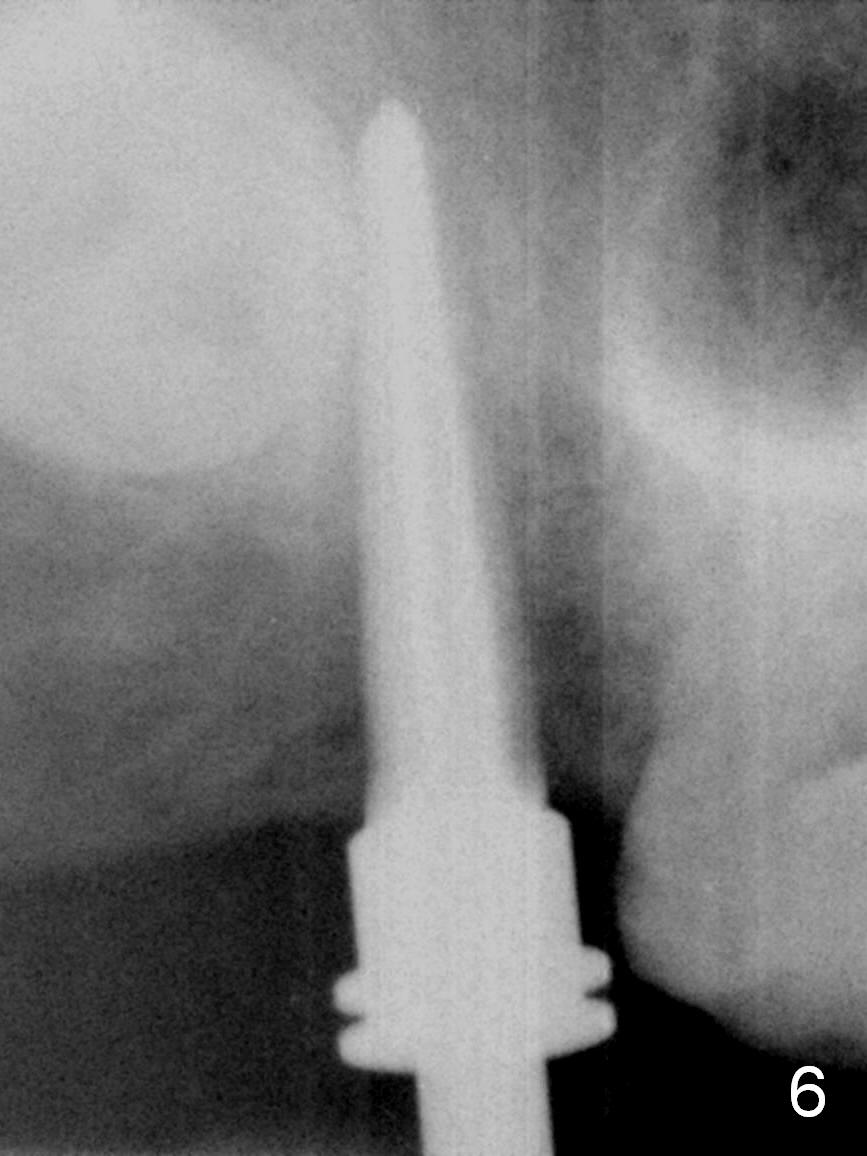

Extraction confirms crack tooth at #2 (Fig.1 (mesial view) <). The buccal (Fig.2 (illustration) B) socket is larger than the palatal (P) one, while the septum (S) is small. Osteotomy is initiated on the buccal slope of the septum (Fig.3 red arrow), followed by Magic osteotomes (Fig.4-7). As the diameter of the osteotomes increases, so does the depth with sinus lift (Fig.5 arrow). The largest osteotome is 4.8 mm. When a 5x13 mm implant is placed, it has low torque (Fig.8,9). The implant resists lateral movement, but keeps turning. When a largest pair abutment with the longest cuff is placed (6.5x4(4) mm to hold an immediate provisional in place), it seems to turn with the underlying implant together for a half turn. Since the provisional is engaged into the distal undercut of the tooth #3 (while the acrylic is setting), it may increase the implant stability. Anyway, overprep in this case leads to low primary stability. For immediate implant, underprep is a must. For this case, the last osteotome should have been 4.3 mm (.7 mm (one or two size(s)) smaller than the implant). When the implant is found to have low torque value, remove it, place bone graft in the osteotomy site and surrounding socket for sinus lift as well and place the implant again. The primary stability should have been increased. Preferably, a larger implant should be used (5.5 mm). Fortunately there is nasal hemorrhage postop. Reexamination of the extracted tooth after being soaked in bleach for 2 days confirms that the mesial (Fig.10 M) and distal (Fig.11 D,12 <) crack lines extend intrapulpally (^).